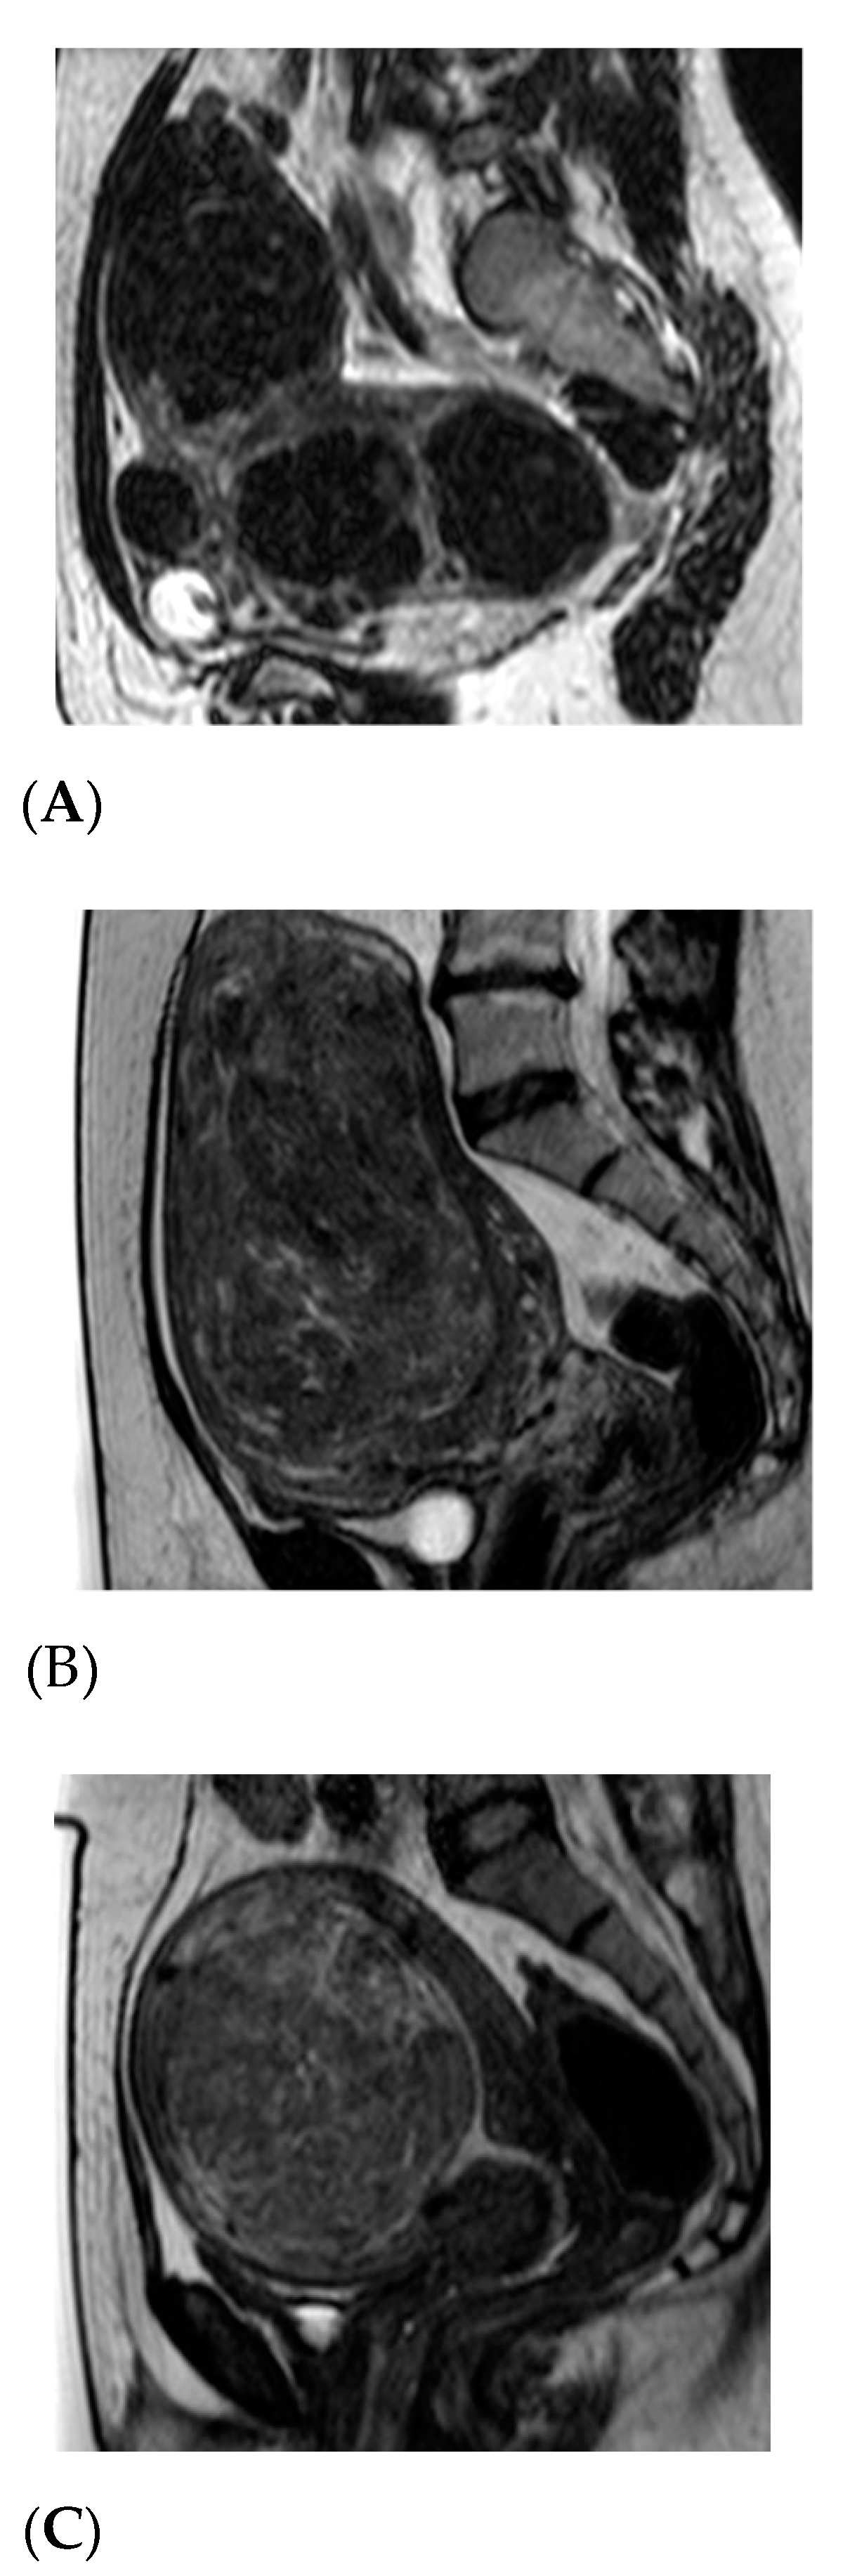

- Funaki, K.; Fukunishi, H.; Funaki, T.; Sawada, K.; Kaji, Y.; Maruo, T. Magnetic resonance-guided focused ultrasound surgery for uterine fibroids: Relationship between the therapeutic effects and signal intensity of preexisting T2-weighted magnetic resonance images. Am. J. Obstet. Gynecol. 2007, 196, 184.e1. [Google Scholar] [CrossRef]

- Geraci, L.; Napoli, A.; Catalano, C.; Midiri, M.; Gagliardo, C. Magnetic Resonance Imaging-Guided Focused Ultrasound Surgery for the Treatment of Symptomatic Uterine Fibroids. Case Rep. Radiol. 2017, 2017, 2520989. [Google Scholar] [CrossRef]